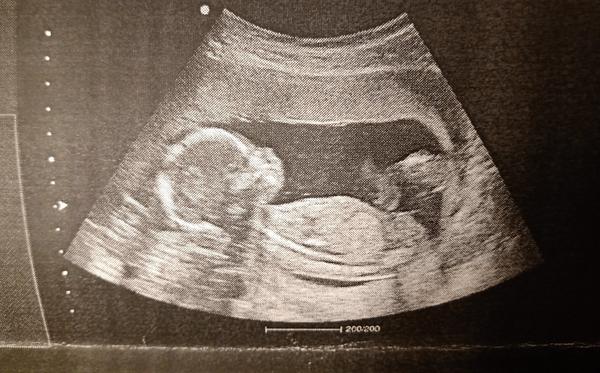

Chlapček alebo dievčatko podľa sona?

Ahojte babizne. Co poviete aké to môže byť pohlavie.

Viete niektora aspoň troska určiť podľa sona? 🙂🙂

@andrea23552 dievča podľa pohlavného hrbolceka sklon nie je 30 %